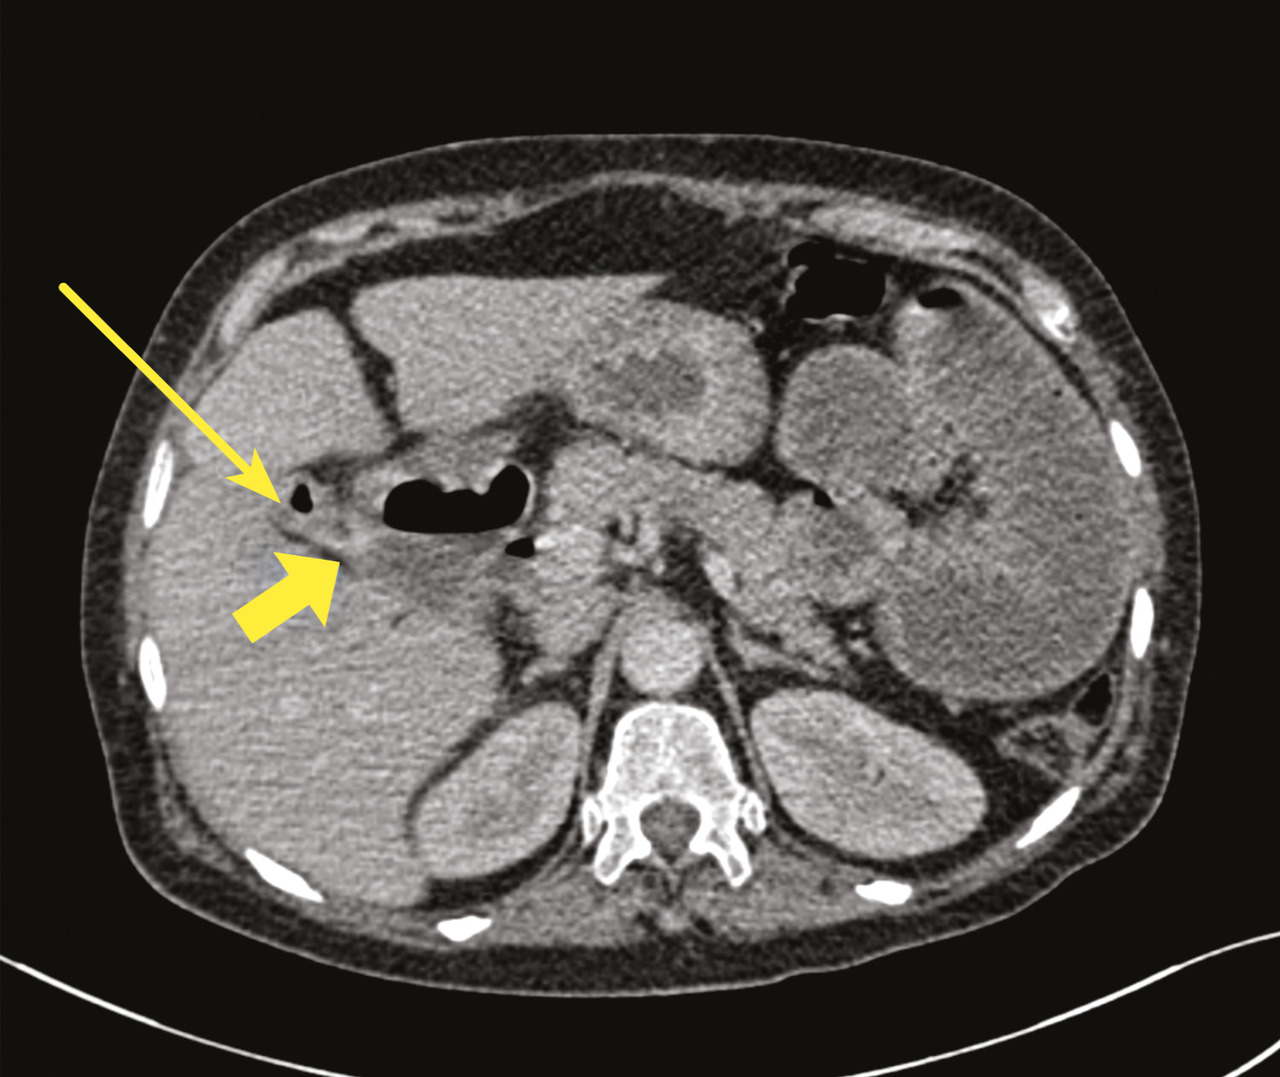

Le diagnostic d’iléus biliaire est posé. La patiente bénéficie d’une entérolithotomie (fig. 4) associée à une cholécystectomie et une cure du trajet fistuleux cholécystoduodénal.